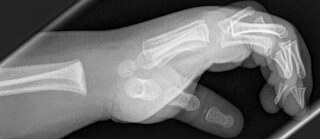

X-rays

CC0